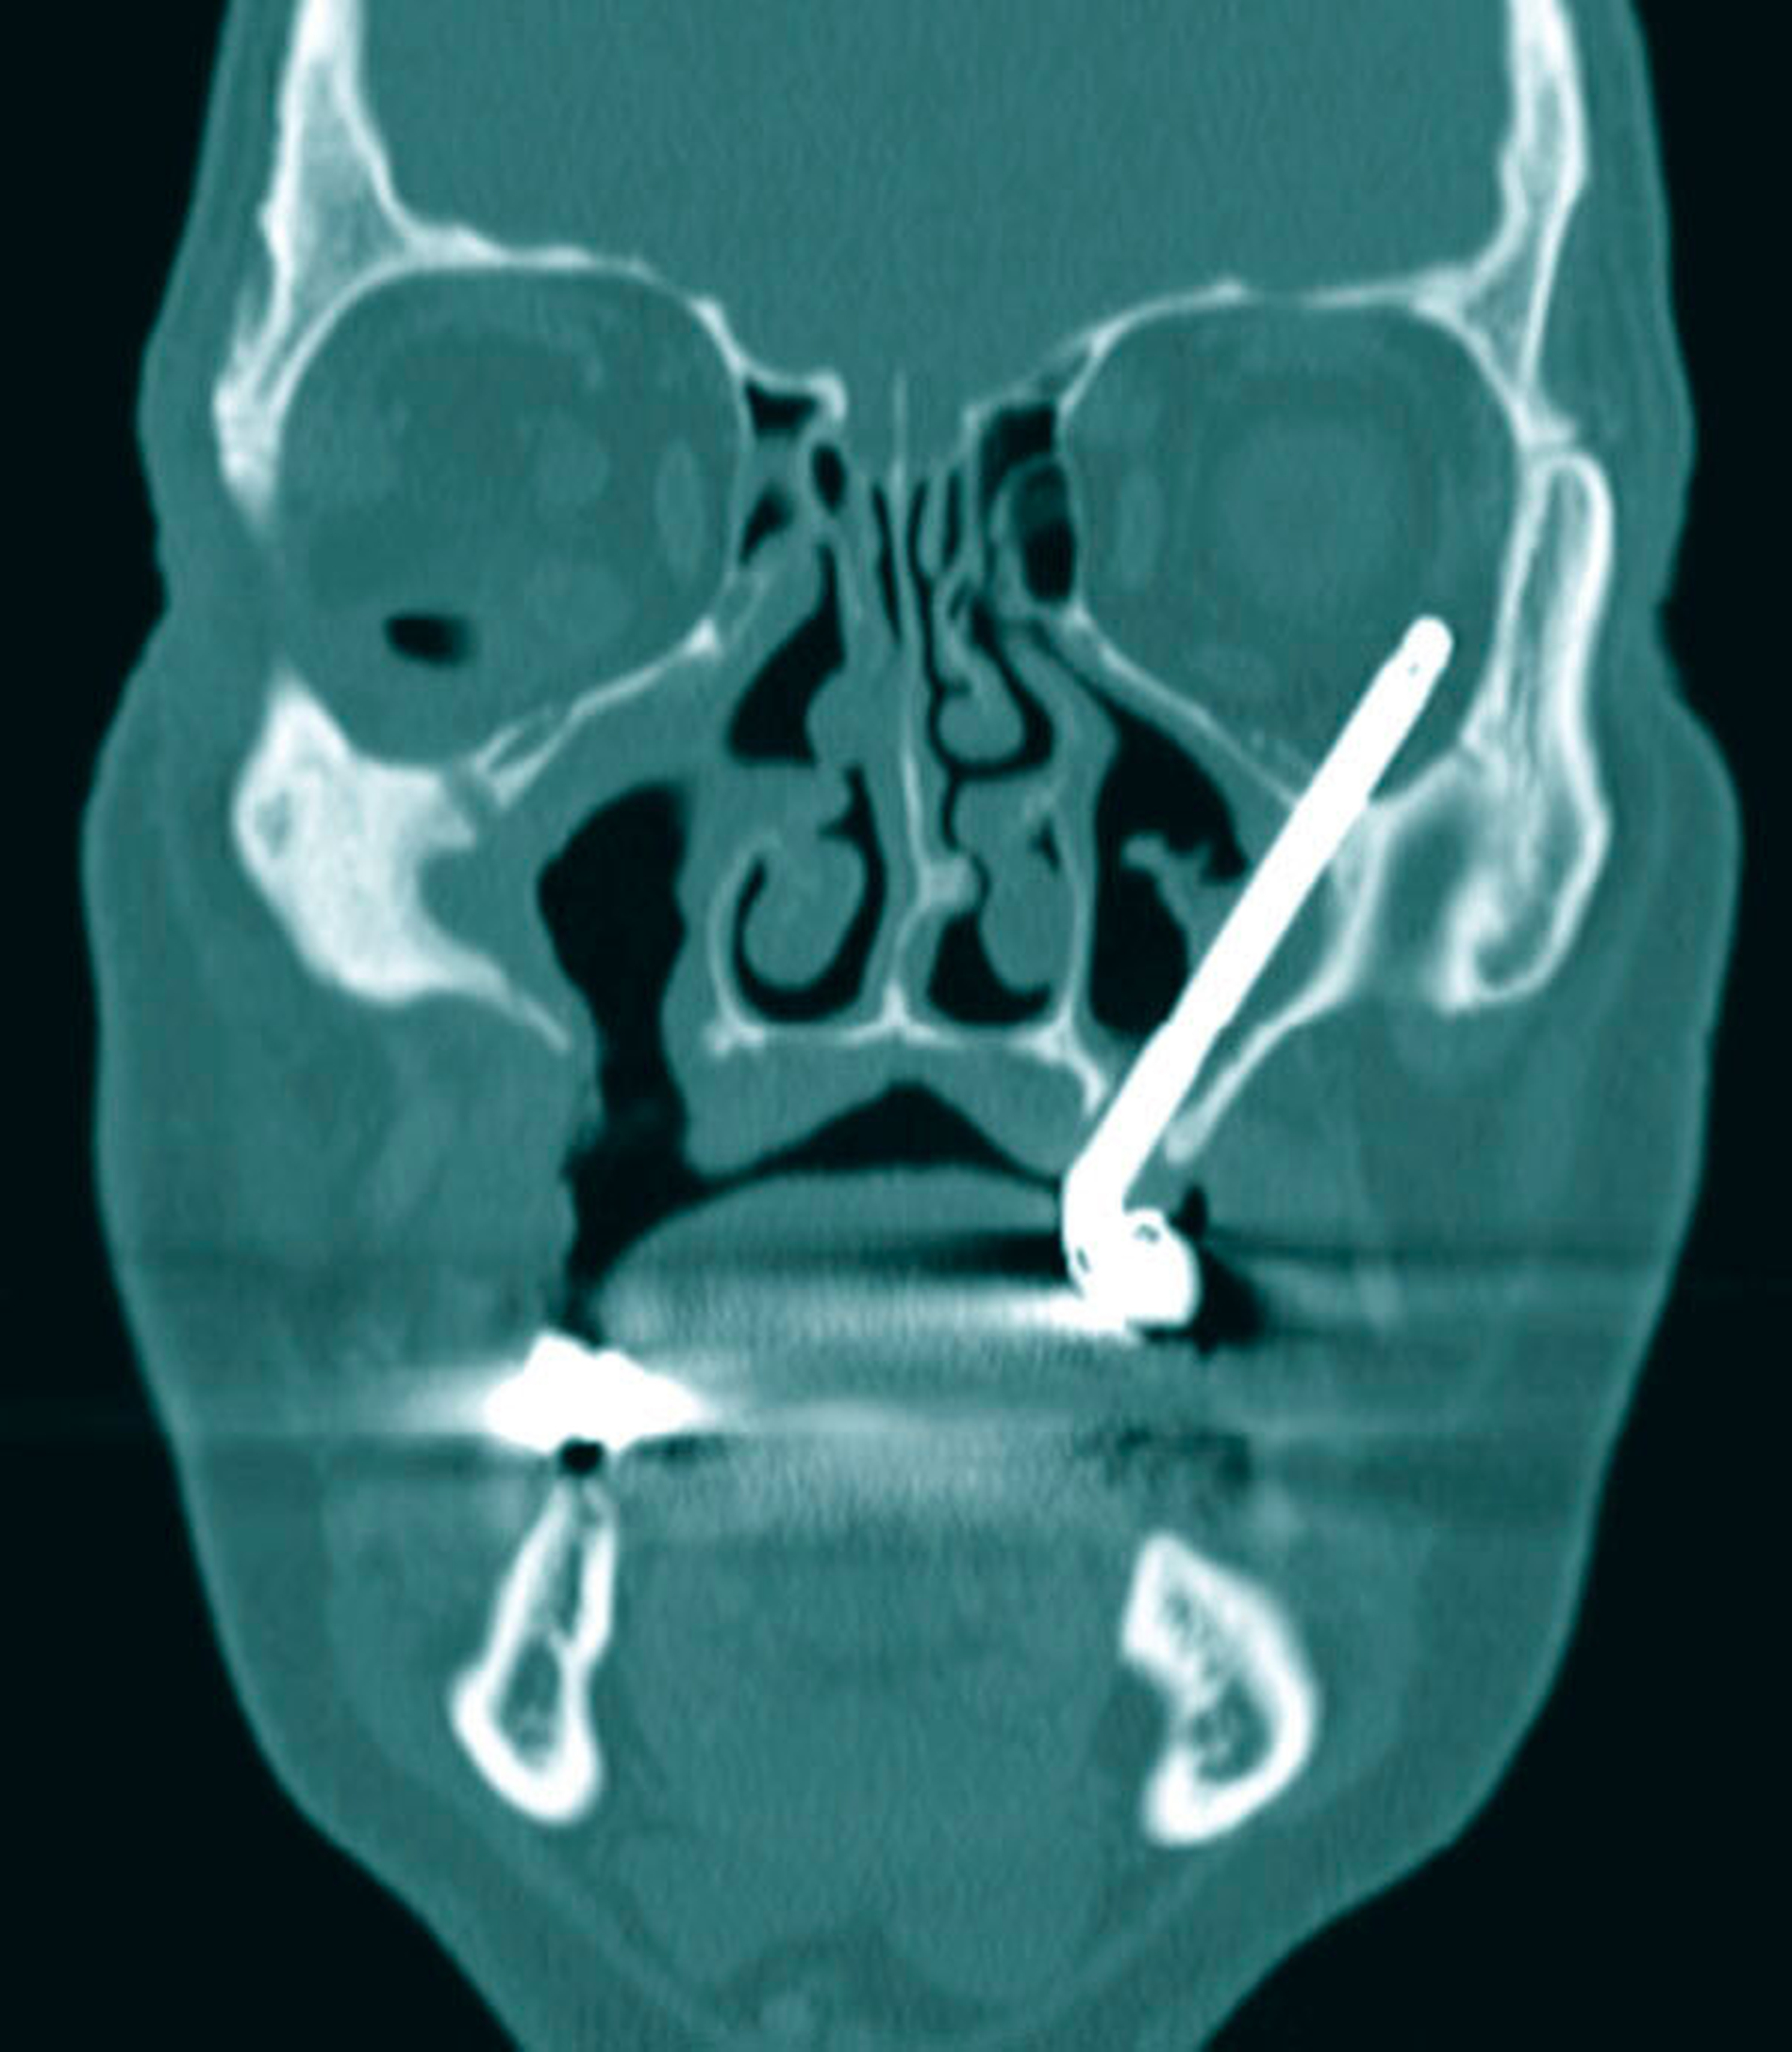

Zur weiteren Abklärung erfolgte nach zweidimensionaler Beurteilung die dreidimensionale Rekonstruktion der CT-Daten. Hierbei kamen die röntgenopaken Implantate im Kiefer sehr gut zur Darstellung und konnten in Bezug auf deren anatomische Lage beurteilt werden. Im atrophen Ober- und Unterkiefer zeigte sich ein mittelgradiger horizontaler Knochenabbau mit vertikalen Einbrüchen an allen Implantaten. In der rechten Maxilla regio 016 bestand nach Explantation eines rechtsseitigen Zygoma-Implantats ein circa 2 cm großer Defekt, der, aufgrund der verdrängten Weichgewebe und Lufteinschlüsse sicher bis in die mittlere, zentrale Orbita reichte.

Als auffälliger Nebenbefund fand sich auch auf der linken Seite ein 60-mm-Zygoma-Implantat, das 17 mm in die linke Augenhöhle ragte. Neu aufgetretene Veränderungen oder Behinderungen in diesem Bereich waren vom Patienten subjektiv nicht wahrgenommen worden, die Implantation selbst lag bereits zehn Jahre zurück.

Das Problem beim Einbringen der Zygoma-Implantate ist die korrekte Positionierung in den Jochbeinkörper. Hier kann es besonders beim liegenden Patienten leicht zu einer Via falsa kommen. Im vorliegenden Fall wurden die 60 mm langen Zygoma-Implantate statt in den Jochbeinkörper beidseits in die Orbita gesetzt. Das Problem der möglichen Fehlpositionierung langer Fixturen und von Zygoma-Implantaten wurde früh erkannt und es wurden hierfür Navigationshilfen entwickelt [Stella et al., 2000]. Schiroli et al. beschrieben 2011 eine Methode zur Computer-navigierten Insertion dieser Implantate. Sie wiesen auf der Basis ihrer Erfahrungen mit 25 Implantaten darauf hin, dass Komplikationen auch mit der Navigation nicht vollständig ausgeschlossen werden können [Schiroli et al., 2011].

Die Einbringung speziell von überlangen dentalen Verankerungselementen im schwierigen Situs oder in anatomisch anspruchsvollen Regionen geht also mit einem erhöhten Risikoprofil einher. Gerade in diesen Fällen ist der Einsatz von adäquaten Hilfsmitteln wie der schablonengesteuerten Implantation oder der Navigation sinnvoll und gegebenenfalls bei schlechter Übersicht auch notwendig. Die Planung des Eingriffs, das operative Vorgehen und die postoperative Überwachung und Kontrolle des Patienten sollten dabei einem strikten Qualitätsmanagement unterliegen. Auch zum damaligen Zeitpunkt waren die Voraussetzungen und Notwendigkeiten gegeben, durch eine dreidimensionale Planung den operativen Prozess an die individuelle Patientensituation anzupassen, um Risiken zu senken und Komplikationen zu vermeiden. Nicht zuletzt hätte eine postoperative radiologische Kontrolle die kompromittierte Implantatposition zweifelsfrei dargestellt. Es ist sicher auch der inerten Eigenschaft des Titans zu verdanken, dass der Patient im Verlauf von zehn Jahren keine weiteren Komplikationen erlitten hat.